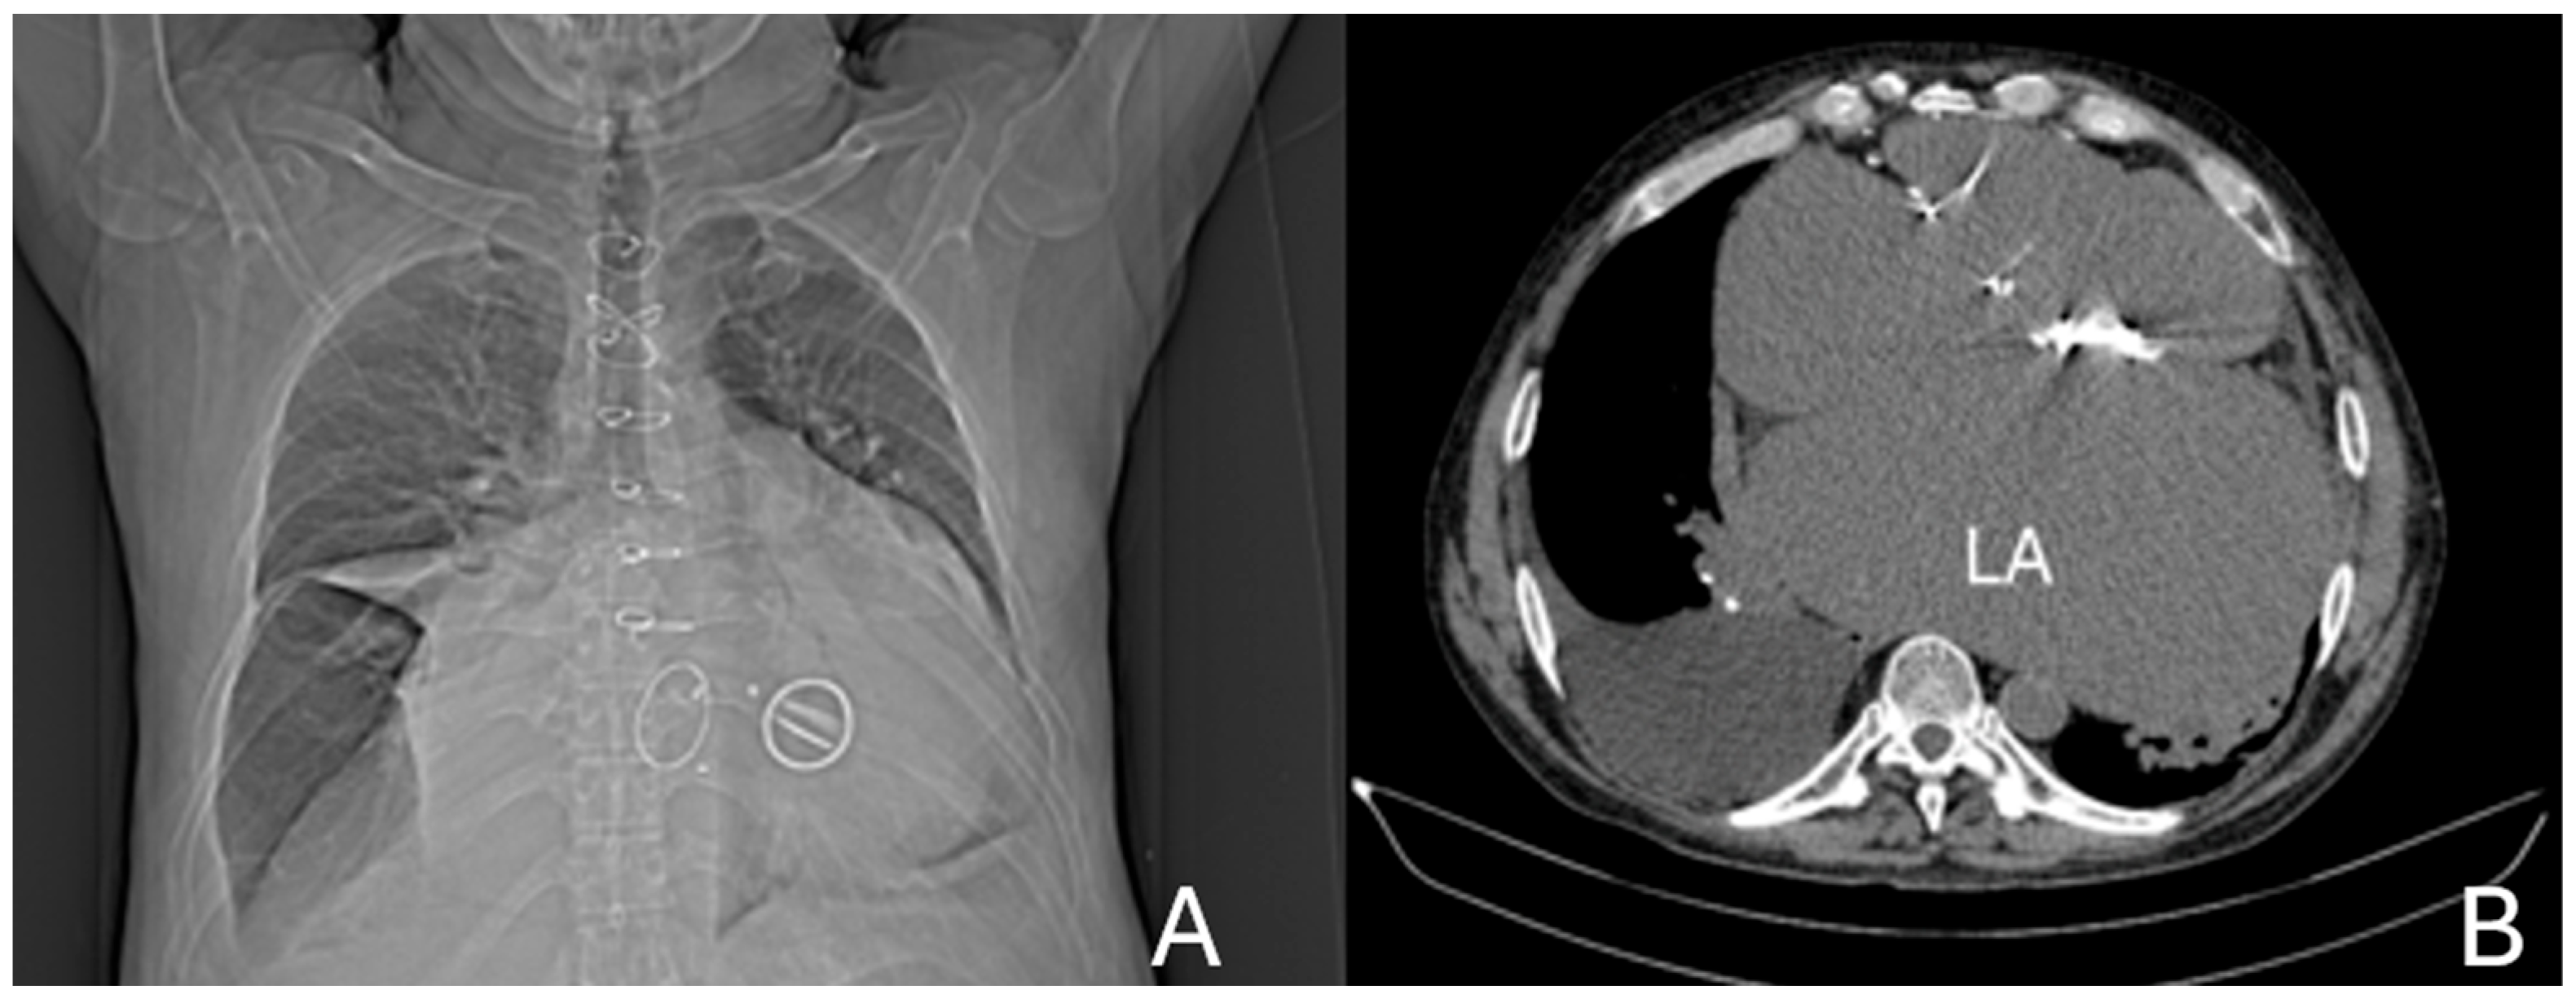

4. Case Presentation